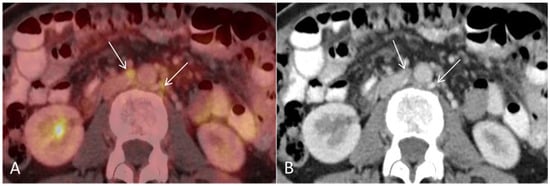

Figure 4. (A) Baseline axial PET/CT fused and (B) axial CT shows several non-enlarged retroperitoneal lymph nodes with high metabolic activity ((A,B), arrows). The lymph nodes were not suspicious for malignancy on CT alone.